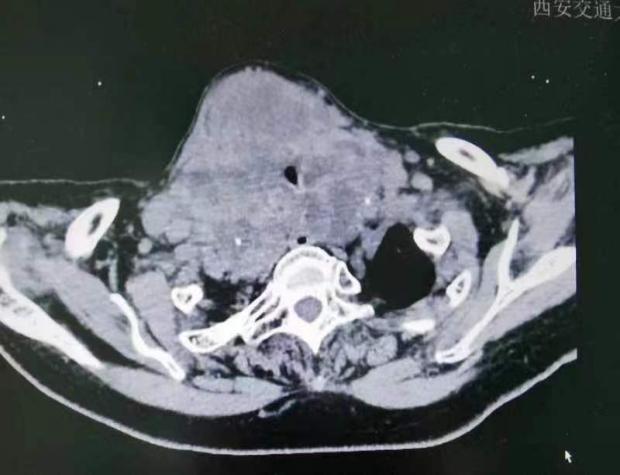

术前影像检查结果显示:气管受到严重压迫